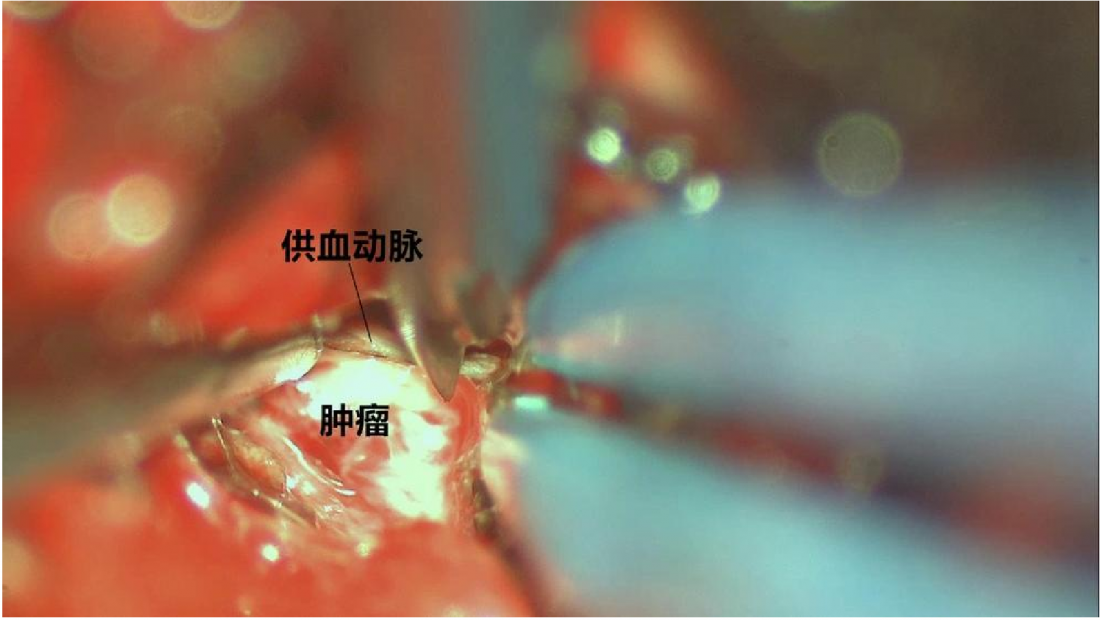

手术入路选择:考虑到患者肿瘤更靠近中线,因此为采取颞下入路及乙状窦后入路。我们采取经枕下正中入路,经第IV脑室切开桥脑,路径最近。因实质性血网手术切除的原则是整体剥除,否则出血汹涌。术中见肿瘤供血丰富,分离肿瘤,完整播出肿瘤。

2、血管网状细胞瘤分为实性及囊性,对于囊性血网的切除原则是切除瘤结节,而非将所有囊壁必须切除。实性血网需要将全部肿瘤部分切除,同时因其血运丰富,手术切除时应整体剥除,而不能分块切除。应该沿着肿瘤的边界仔细分离,因此在脑干内整体剥除肿瘤大大增加了手术的难度。手术时须严格沿肿瘤边界进行,减少对脑干的骚扰。主要最后将肿瘤的供血动脉全部断掉后,才能慢慢取出肿瘤。